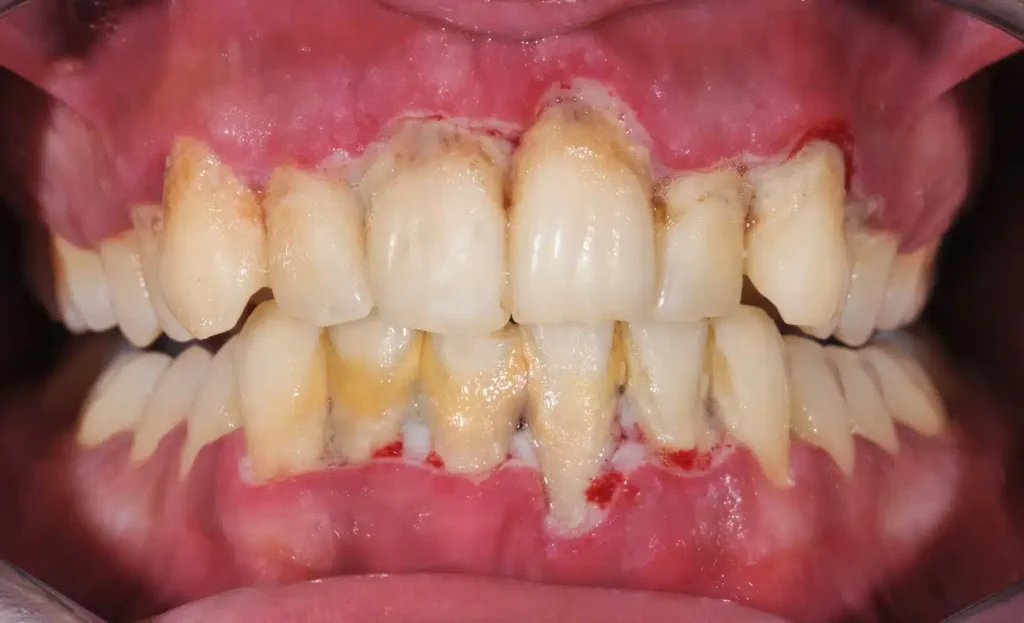

It’s important to note the distinction between gingivitis and periodontitis symptoms (What are the symptoms of gingivitis and periodontitis?). While both involve inflamed gums, periodontitis is marked by additional, more severe signs: gum recession leading to visible tooth roots, the formation of pockets between the teeth and gums where infection thrives, loose teeth, changes in bite, and eventually, tooth loss. Gingivitis is the stage *before* these irreversible changes typically occur, making symptom recognition and early intervention crucial.

Can gum disease be reversed entirely?

Yes, **gingivitis** (the early stage of gum disease) can be reversed entirely. The tissues affected (the gums) can heal back to their original healthy state. However, it is absolutely critical to understand the distinction between gingivitis and periodontitis. **Periodontitis** (the more advanced stage, where the infection has spread to the bone and supporting ligaments) cannot be reversed entirely. The bone and tissue loss that occurs in periodontitis is permanent. While treatment for periodontitis can stop or slow down the progression of the disease and manage the condition, it cannot regrow the lost support structures. So, when people ask “can gum disease be reversed?”, the answer is yes, *if* it’s caught at the gingivitis stage. Once it progresses to periodontitis, the focus shifts from reversal to management and prevention of further damage.

Is gingivitis permanent if left untreated?

Gingivitis itself is not permanent in the sense that the inflammation is *always* there at the same level. However, if left untreated, it is highly likely to progress. Think of it as an untreated infection. The body might try to fight it, but without removing the source (plaque/calculus), the battle is lost. Left unchecked, the chronic inflammation will gradually spread from the gums to the deeper supporting structures of the teeth – the periodontal ligaments and the alveolar bone. When this happens, the condition has progressed from gingivitis to periodontitis. Periodontitis *does* cause permanent damage (bone loss, tissue loss). So, while gingivitis isn’t *inherently* permanent as inflammation, its untreated state almost inevitably leads to the permanent damage characteristic of periodontitis. It’s the critical, reversible gateway. Ignoring it means accepting the high probability of progressing to irreversible problems.